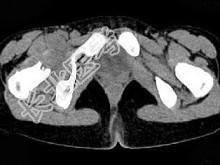

- 单项选择题女,11岁, 肺部有结核病史,二个月前右髋关节有外伤史, 右髋关节部逐渐肿胀疼痛,休息后可减轻, 结合图像,最可能的诊断是 ( )

A、右髋关节结核

B、化脓性关节炎

C、右髋关节退行性变

D、右髋关节类风湿关节炎

E、右髋关节痛风